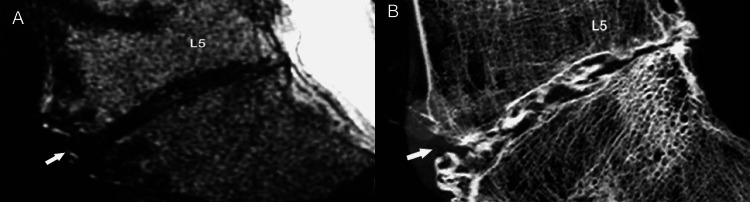

Within the range of disc degeneration concomitant degenerative alterations in the vertebral end-plates are classified into three categories based on distinctive MR imaging characteristic [7,19-22]. Type I end-plate changes appear as low signal intensity on T1-weighted images and high signal intensity on T2-weighted images, reflecting the presence of fibrovascular tissue in the abnormal end-plate. Type II degenerative end-plate changes are visualized as high signal intensity on T1-weighted images and decreased signal intensity on T2-weighted images, owing to the deposition of adipose tissue in bone marrow. Type III end-plate changes are seen as low signal intensity on both T1-weighted and T2-weighted images, consistent with prominent hyperostosis that has replaced normal marrow (Figures 13A-13F).

Figure 13. End-plate changes.

(A, B) Sagittal T1- and T2-weighted MR images show Modic type 1 end-plate marrow changes (arrow) of low and high signal intensity, respectively corresponding to the formation of fibrovascular tissue.

(C, D) Sagittal T1- and T2-weighted MR images show Modic type 2 end-plate marrow changes (arrow) of high signal intensity corresponding to fatty marrow.

(E, F) Sagittal T1- and T2-weighted MR images show Modic type 3 end-plate marrow changes (arrow) of low signal intensity corresponding to the formation of fibro-osseous tissue.